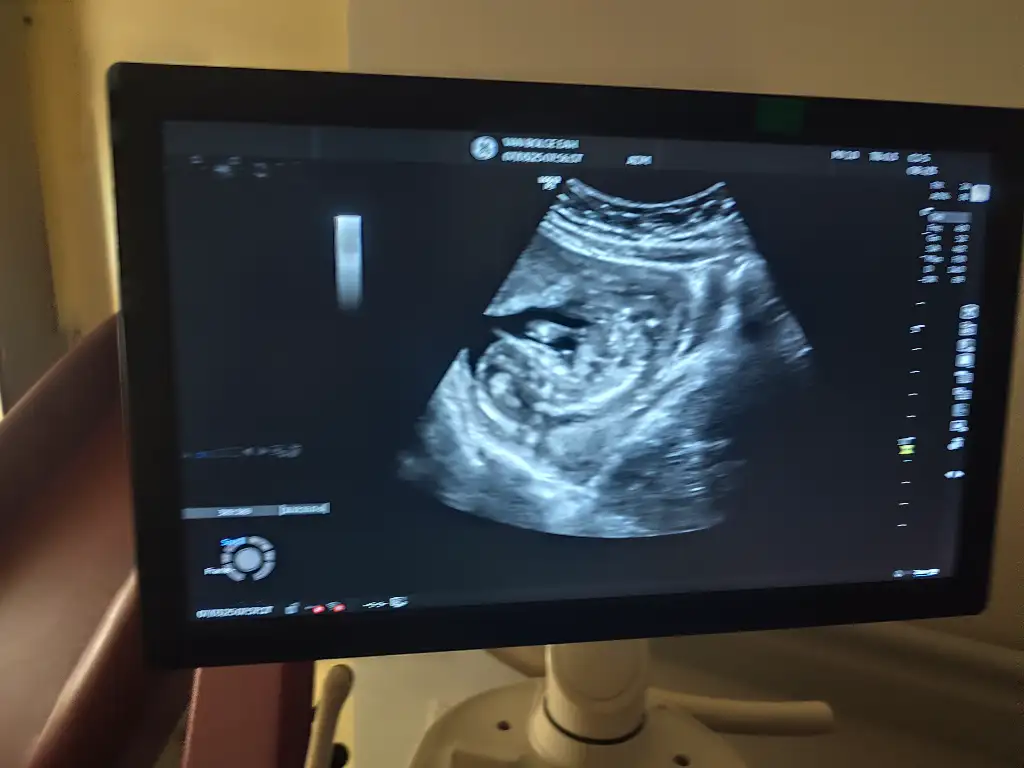

Benim bebeğime de bakar mısınız ultrasonda gostermiyor kendiniMerhaba erkek gibi duruyor

Merhabalar erkek gibi duruyor ama nubda tam aci tam yukari degil hafif yukari skull teorisine gorede erkek gibi duruyor ama tab i Rabbim gonlunuze gore versin insallah tahminim bu Allah bilir gerisini saygilar